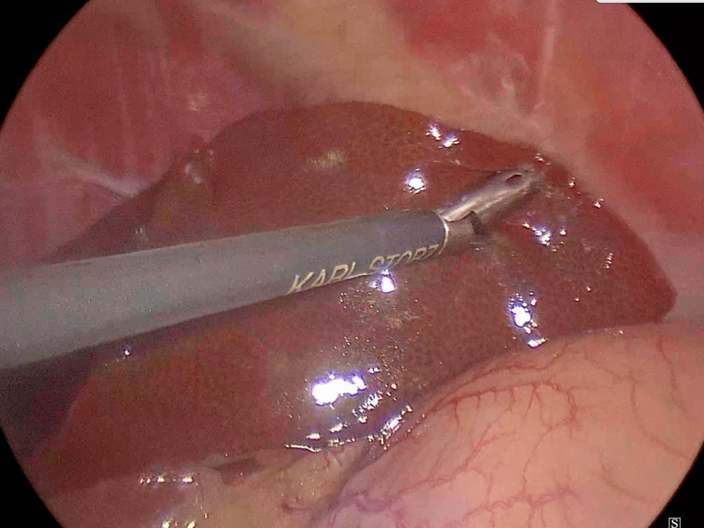

手術の様子

転移を確認するための肝生検の実施